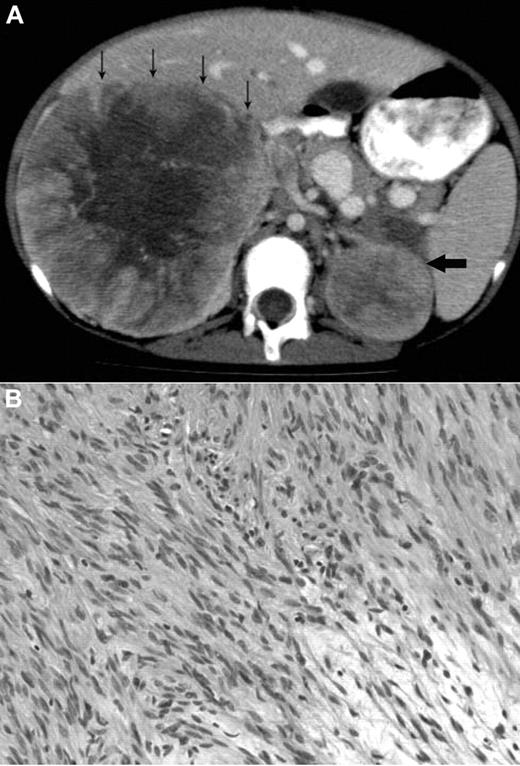

A 12-year-old Metis, Canadian aboriginal group, female presented with a 2-month history of abdominal and back pain with decreased energy. Her medical history included presumed fetal alcohol syndrome with moderate to severe developmental delay, cutis laxa with aortic root dilation, anemia secondary to celiac disease, and seizures. She did not have recurrent or unusual infections. Physical examination at diagnosis showed palpable masses confirmed to be bilateral adrenal masses on abdominal CT scan (Figure 1A). The parents provided written informed consent for the studies in accordance with the Declaration of Helsinki and publication of results per Children's Hospital of Philadelphia Institutional Review Board approval requirements.

Radiologic and histologic findings. (A) Axial CT view of the upper abdomen after intravenous contrast injection and oral contrast administration: Large solid mass in the right suprarenal region with faint central calcification and central stellar hypodensity. Small arrows indicate the anterior border of this mass. The smaller more homogeneous solid lesion in the left suprarenal region is indicated by one large arrow. The right-sided lesion displaces the inferior vena cava anteriorly and medially, and there is visibility of an intracaval defect corresponding to a clot. (B) H&E stain showing elongated spindle cells arranged in a storiform pattern admixed with scattered chronic inflammatory cells (original magnification ×400). The images were captured digitally through a Nikion Eclipse i80 microscope (Nikon) with a 40×/0.75 objective at room temperature without flourochromes. The camera was a Pixelink PL-SW Microscopy (Canimpex Enterprise Ltd) with acquisition software of Pixelink Capture SE Version 4 software for Windows XP (Canimpex Enterprise Ltd). No subsequent image reprocessing occurred.

The microscopic findings in the left and right adrenal tumors were diagnostic of EBV-SMTs7,8 (Figure 1B). Elongated spindle cells with eosinophilic cytoplasm were present along with inflammatory cells, including lymphocytes and histiocytes. The endothelial cell lining was in a hemangiopericytoma-like pattern. Immunoperoxidase staining demonstrated positive vimetin, smooth muscle actin, and desmin, all specific findings in SMTs.8 Lastly, in situ hybridization for EBV early RNAs produced strong and diffuse reactivity in addition to positive nuclear staining of EBV early RNAs. An initial tumor biopsy showed a translocation t(4;21) (q21:q11.2) but was not replicated in subsequent cytogenetic cultures and is of uncertain significance. Constitutional chromosomes were normal.